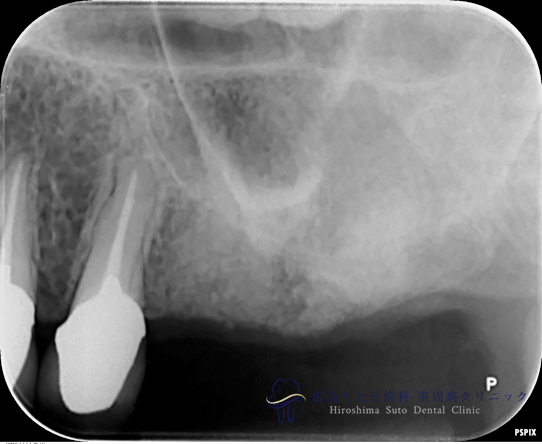

術中

手術直後のレントゲン

6ヶ月後のレントゲン写真

インプラント手術時

インプラント手術中

術後(インプラント治療後)

| 治療名 | GBR(骨再生誘導療法)、インプラント治療(2本分) |

|---|---|

| 治療説明 | 左上の奥歯に歯茎の腫れがあり、診査の結果歯根が破折しておりました。抜歯後はインプラント治療を希望されたため、抜歯後、失われた歯槽骨を増生するためにGBRを行い、インプラント治療を行いました。 |

| 治療回数・期間 | 約10ヶ月(歯周基本治療、抜歯、GBR、インプラント治療) |

| 副作用とリスク | 歯周外科後には一時的に術後に腫れや仏痛や出血が発現することがあります。 治癒の状態によって治療期間が長くかかる場合があります。 |

| 料金 | 104.5万円 |